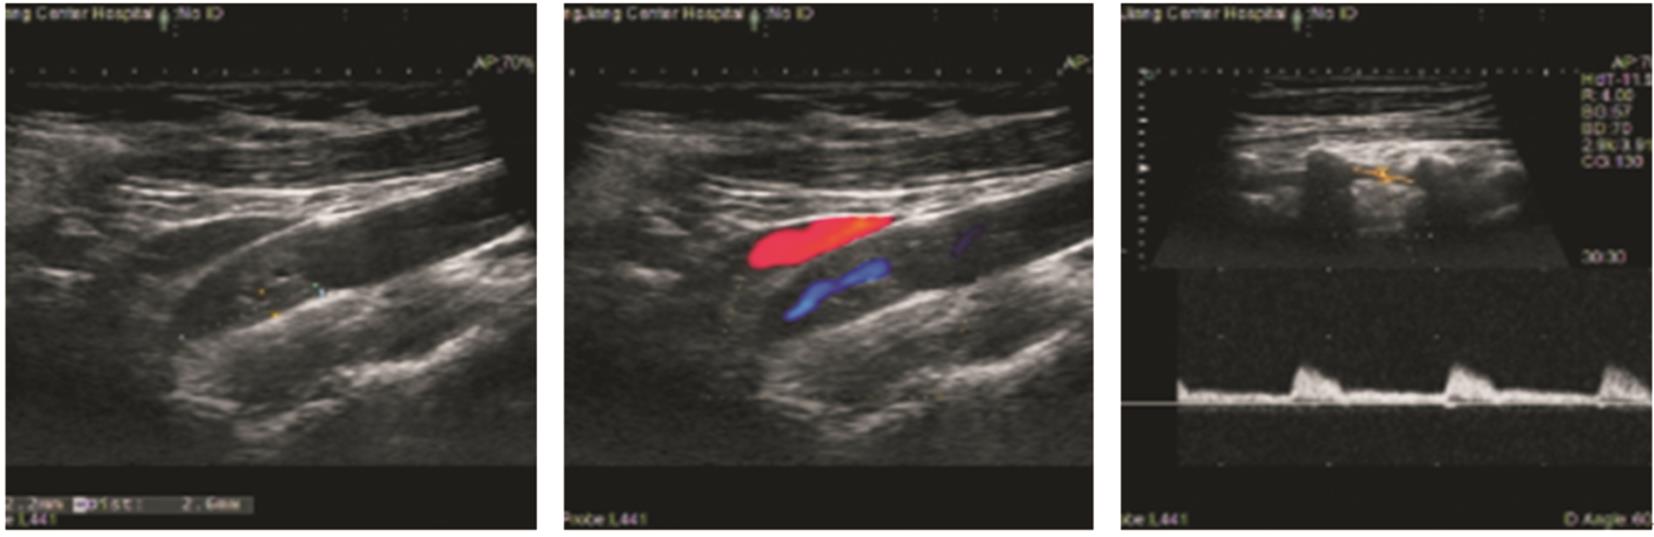

该文追踪1例低叶酸血症患者6年,观察患者体内血栓的动态演变过程。对该例患者进行了叶酸水平、同型半胱氨酸、维生素B12水平监测,同时监测患者的颈动脉超声、下肢动脉超声、头颅磁共振成像和磁共振血管成像,并获得患者的基因学检测结果。第1年,患者出现了左侧大脑中动脉皮质支闭塞(叶酸2.23 ng/mL)。第2年,患者出现了左下肢深静脉血栓(叶酸2.58 ng/mL)。第3年,患者出现左侧颈内动脉颅内段大部分闭塞(叶酸2.16 ng/mL)。第4年,患者出现右下肢深静脉血栓+左侧颈内动脉颅外段狭窄+右下肺静脉血栓形成(叶酸2.27 ng/mL),此时启动了补充叶酸治疗。第5年,患者未再新发血栓。采用DNA微阵列法检测发现,该例患者基因组中MTHFR基因677位为T/T纯合型(突变型)。第6年,患者死于肺炎。该类型突变的患者会出现低叶酸血症,导致快速侵袭性、全身动静脉多发性血栓,补充叶酸治疗可能有效。

A patient with hypofolatemia was followed up for 6 years to observe the dynamic evolution of thrombus. The levels of folic acid, homocysteine, and vitamin B12 were monitored, as well as carotid artery ultrasound, lower extremity arterial ultrasound, cranial MRI, and MRA, and genetic testing results were obtained. The patient experienced occlusion of the cortical branch of the left middle cerebral artery (folic acid 2.23 ng/mL) in the first year, deep vein thrombosis of the left lower extremity (folic acid 2.58 ng/mL) in the second year, and occlusion of most of the intracranial segment of the left internal carotid artery (folic acid 2.16 ng/mL) in the third year. In the fourth year, the patient experienced deep vein thrombosis of the right lower extremity, stenosis of the extracranial segment of the left internal carotid artery, and venous thrombosis of the right lower lung, with a folic acid level of 2.27 ng/mL, and folate supplementation was initiated at this time. New-onset thrombus was not observed in this patient in the fifth year. DNA microarray analysis showed T/T homozygous type (mutant type) at the 677 locus of the MTHFR gene. The patient died of pneumonia in the sixth year. Patients with such mutation may develop hypofolatemia, leading to rapidly aggressive multiple arteriovenous thrombosis throughout the body, and folate supplementation might be an effective treatment method.

图4 右侧下肢深静脉超声图像Fig.4

图5 颈动脉超声和椎动脉超声图像Fig.5